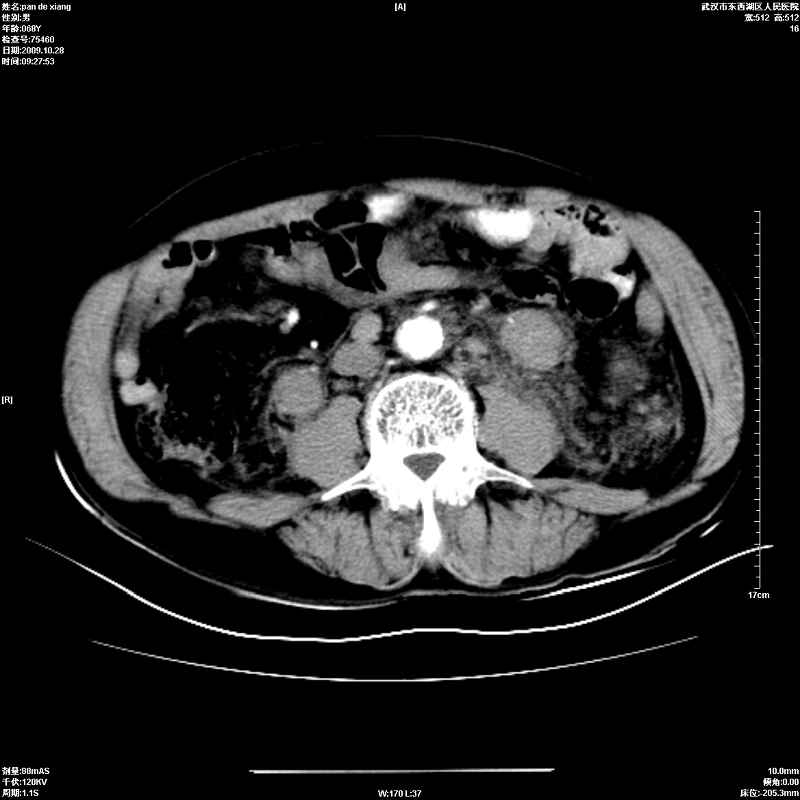

以下是引用杀毒软件在2009-10-28 20:41:00的发言:[br]结合临床考虑---白血病双肾改变或淋巴瘤。

以下是引用zxl51642在2009-10-29 9:59:00的发言:[br]结合临床“单克隆免疫球蛋白血症”,考虑双肾为继发损害并肾功能不全(尿中大量igg及少量iga、igm等大分子免疫球蛋白滤出所致继发损害),椎前软组织肿块为髓外造血。与浆细胞瘤有区别,平扫时有战友说的很清楚。